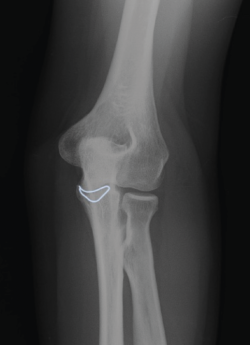

Presentamos el caso de una mujer de 46 años, diestra, sin patología crónica y que trabaja como auxiliar en una residencia geriátrica. Durante su jornada laboral sufre una caída casual presentando dolor y limitación funcional en su codo izquierdo. No presenta deformidades externas en el codo, ni lesiones vasculonerviosas. En el estudio radiológico, se sospecha una fractura de la punta de la apófisis coronoides del codo izquierdo, que correspondería, según la clasificación de Regan y Morrey, al tipo 1 (Figuras 1 y 2). Se comprueba que el codo es estable y se coloca una férula braquial, a la espera de realizar una tomografía computarizada (TC), que confirma la lesión. En la TC podemos visualizar mejor la morfología de la fractura de coronoides tanto en los cortes sagitales (Figura 3), como en los axiales (Figura 4).

Figura 1. Radiografía lateral del codo izquierdo. La silueta señalada corresponde a la fractura de la punta de la apófisis coronoides el día de la caída.

Figura 2. Radiografía anteroposterior del codo izquierdo. Se enmarca la línea de fractura de la apófisis coronoides que se extiende hacia ambos lados hacia la base de la misma.